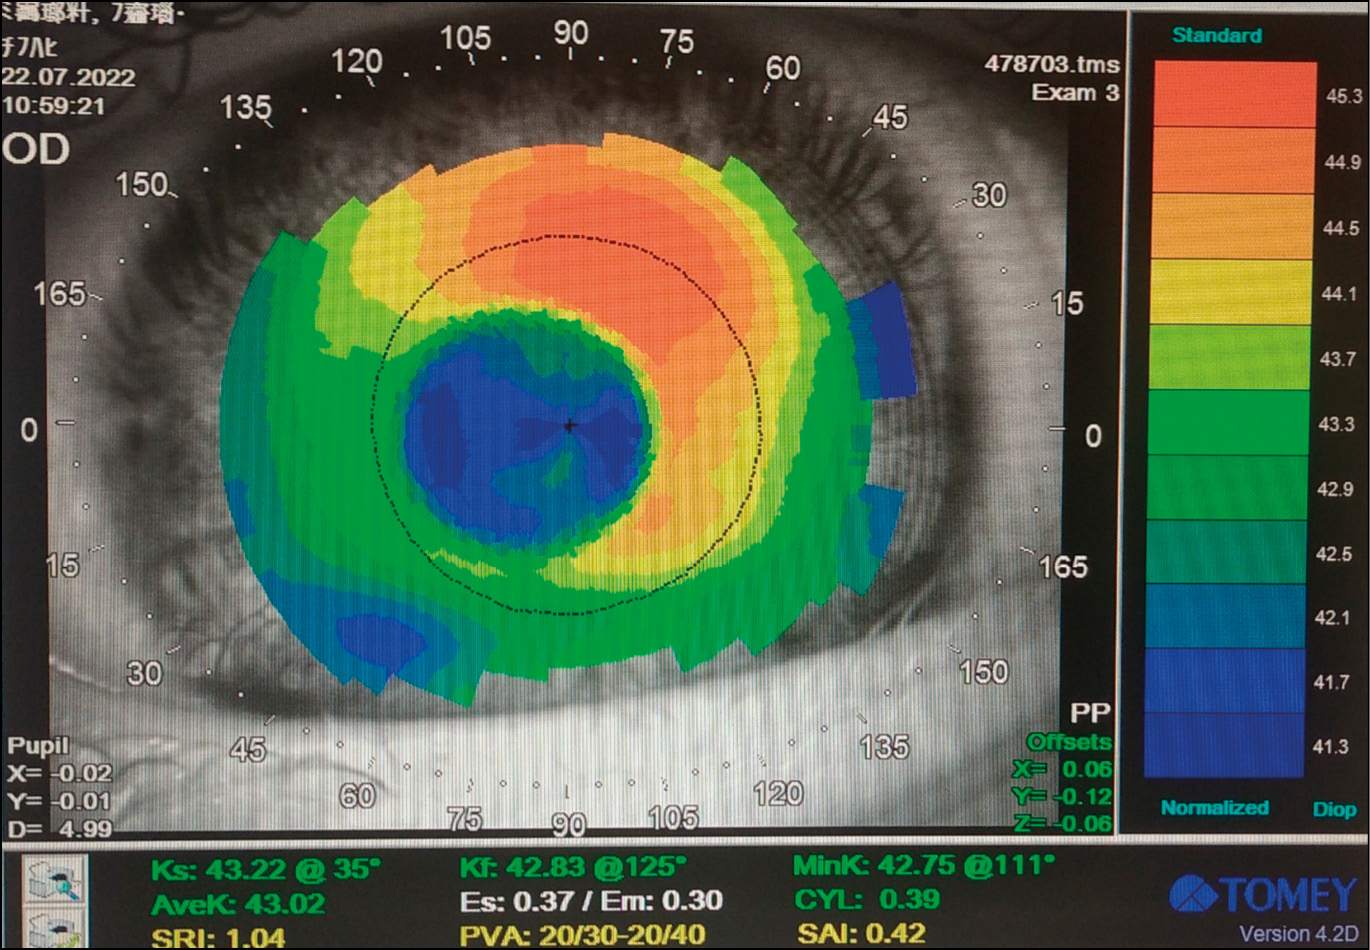

Кератотопографию проводили на приборе TMS-4 (Япония) в БМКЛ и без линз.

Изменение периферической рефракции глаз с миопией в результате наведённого БМКЛ с аддидацией 4,0 дптр миопического дефокуса было отмечено в наших предыдущих работах [3, 7]. Нами было доказано формирование относительной периферической миопии порядка -2,5–3,0 дптр в зоне 15° к виску и к носу от центра фовеа и уменьшение этого дефокуса до (-)1,5–(-)0,5 дптр при удалении на 30° от центра. В настоящей работе была впервые исследована «ближняя периферия», т.е. 5 и 10 градусов от центра фовеа. Результаты убедительно показывают достижение основной цели данного вида коррекции, а именно, устранения исходного гиперметропического дефокуса, свойственного глазам с миопией, и наведение миопического. Сдвиг периферической рефракции в сторону миопии при надевании БМКЛ составил 1,65 дптр в зоне Т15°, 1,72 дптр — в Т10°, 1,04 дптр — в Т5°, 1,46 дптр — в зоне N15° (см. табл. 2). В зоне N10° исходный слабый гиперметропический дефокус в линзах остался без изменений, а в N5° он увеличился на 0,81 дптр. Эти факты, очевидно, следует связать с особенностями посадки БМКЛ, её смещением, что отчасти подтверждается данными кератотопографии (рис. 1).

Рис. 1. Кератотопограмма пациента в бифокальных мягких контактных линзах.